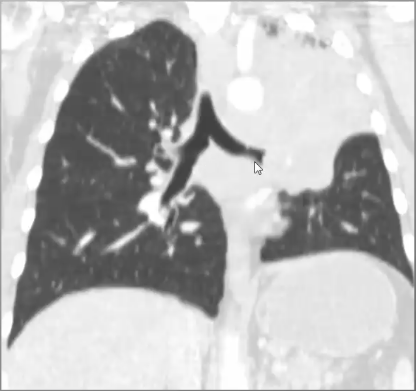

Obstructive atelectasis because NO air bronchogram caused by bronchogenic carcinoma

Looks like pneumonia but there is NO air bronchogram